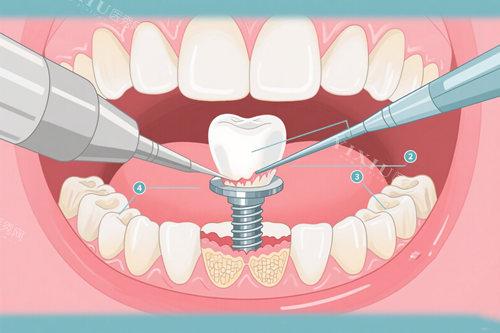

一、种植牙项目

国产种植牙:4380元起/颗

韩国登腾种植牙:5800元起/颗

韩国奥齿泰种植牙:6500元起/颗

美国皓圣种植牙:8500元起/颗

瑞士ITI种植牙:11800元起/颗

瑞典诺贝尔种植牙:10800元起/颗